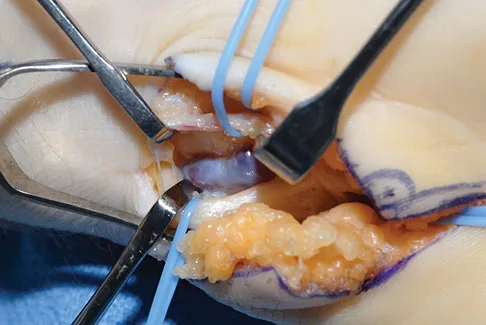

A 39-year-old man has anterior shoulder pain after landing on his abducted left shoulder while playing softball. Examination reveals a stable glenohumeral joint, pain on passive external rotation of greater than 25 degrees, and pain and weakness on belly press (Napoleon's) test. An MRI scan is shown in Figure 32. To provide maximum pain relief and return of function, management should include

Explanation